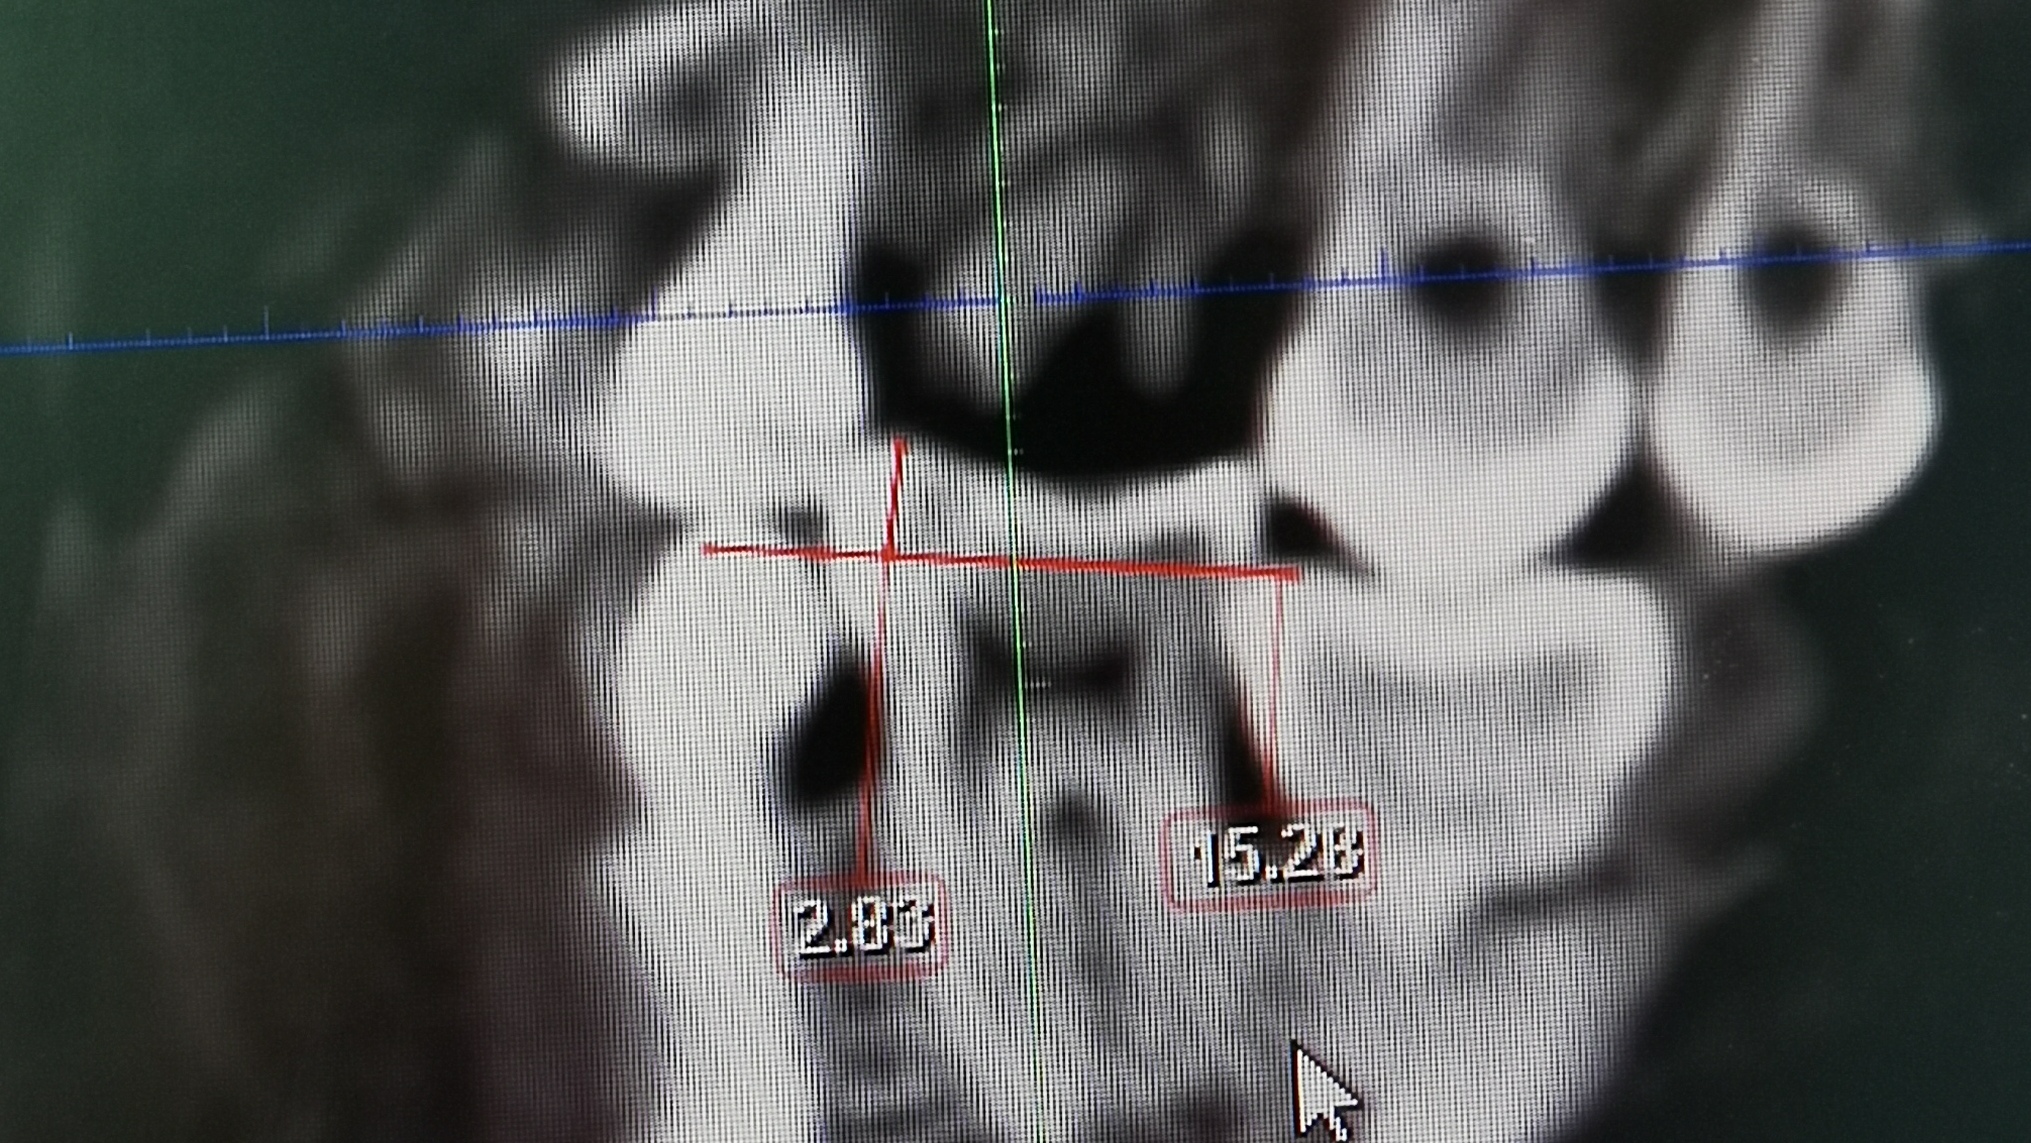

3、阻生智齿

长智齿的时候前面牙会受到压力邻牙或门牙有会被顶歪的可能